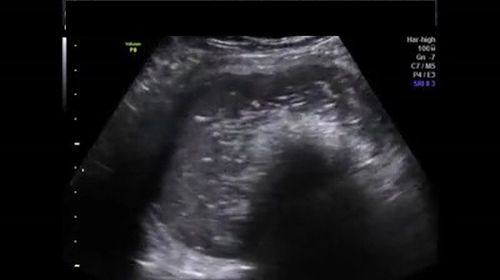

Challenge your diagnostic skills: What’s odd about this 16-week pregnancy?